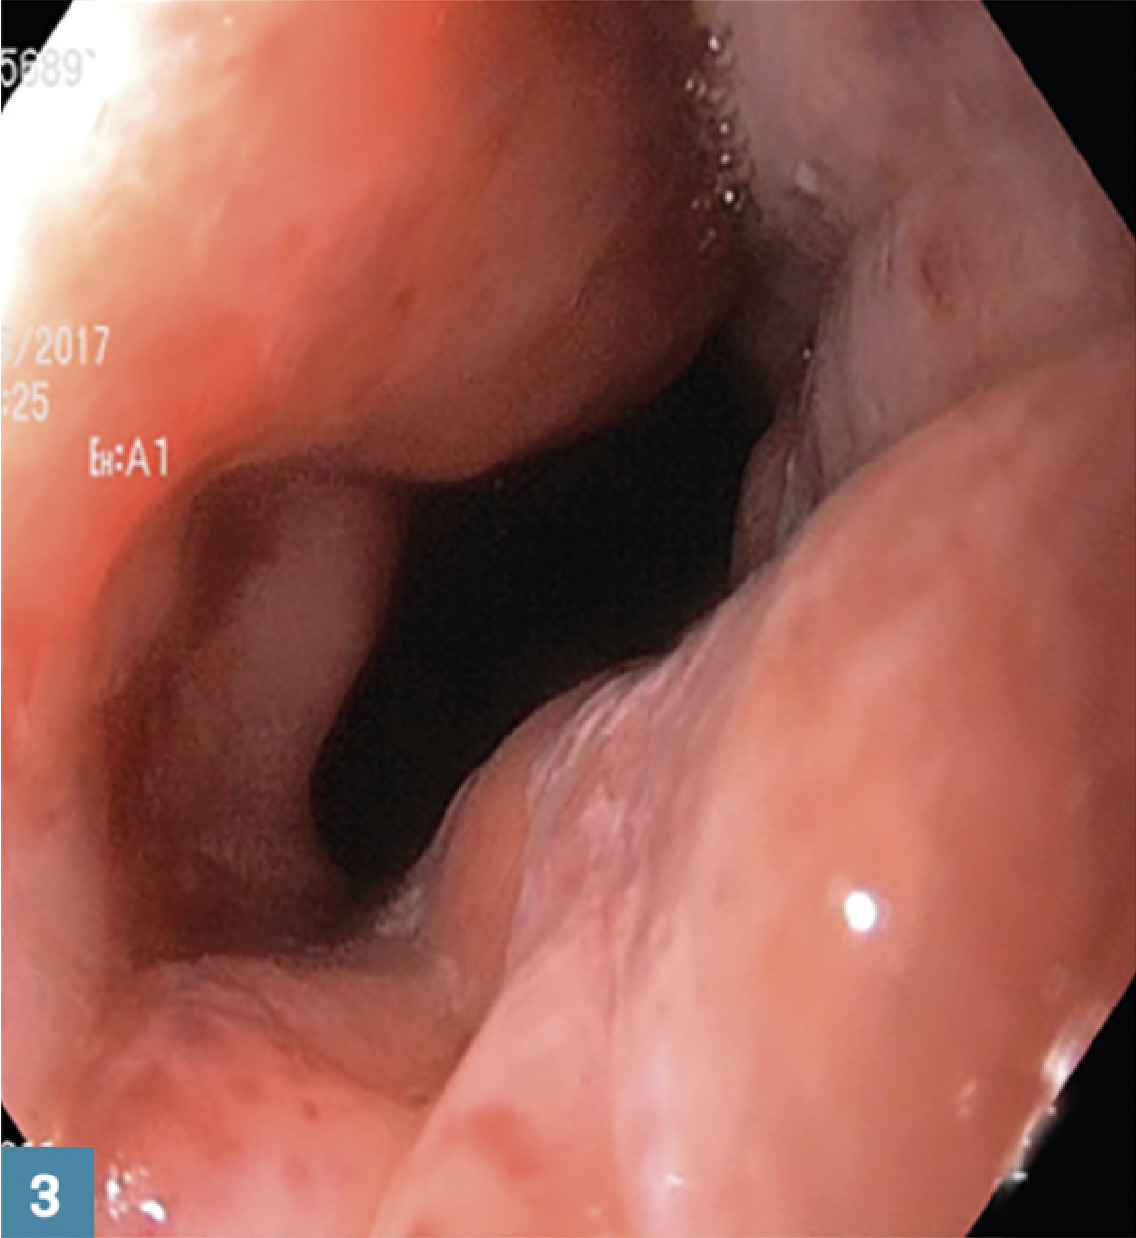

3 Après dilatation pneumatique : aspect béant avec lésions muqueuses superficielles de la jonction œsogastrique.

2. 3 Après dilatation pneumatique : aspect béant avec lésions muqueuses superficielles de la jonction œsogastrique.